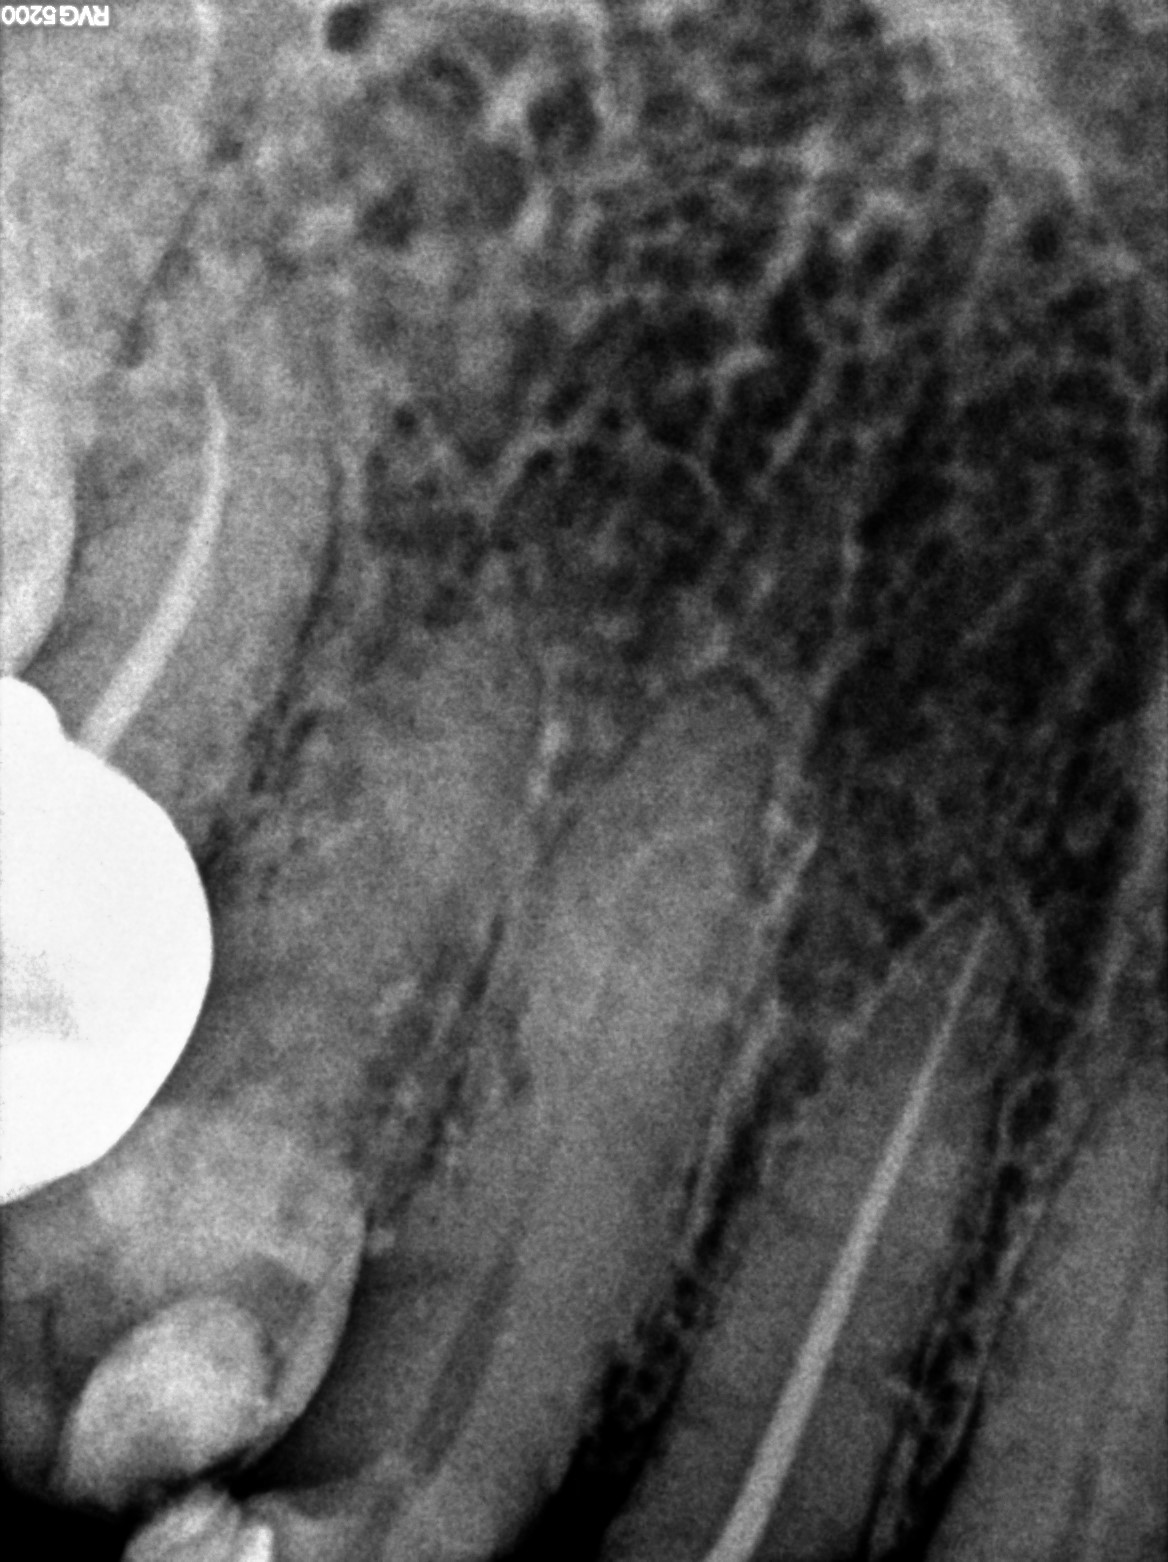

Dental Radiographs FHIR: DocumentReference · LOINC 24641-7

d (14).jpg

24641-7